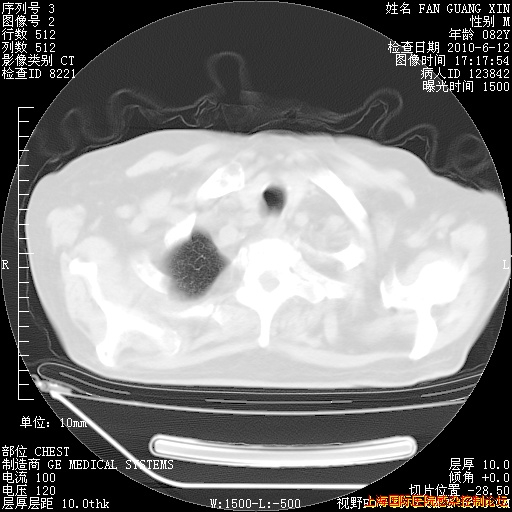

6月12日肺窗

补发6月12日肺部CT肺窗